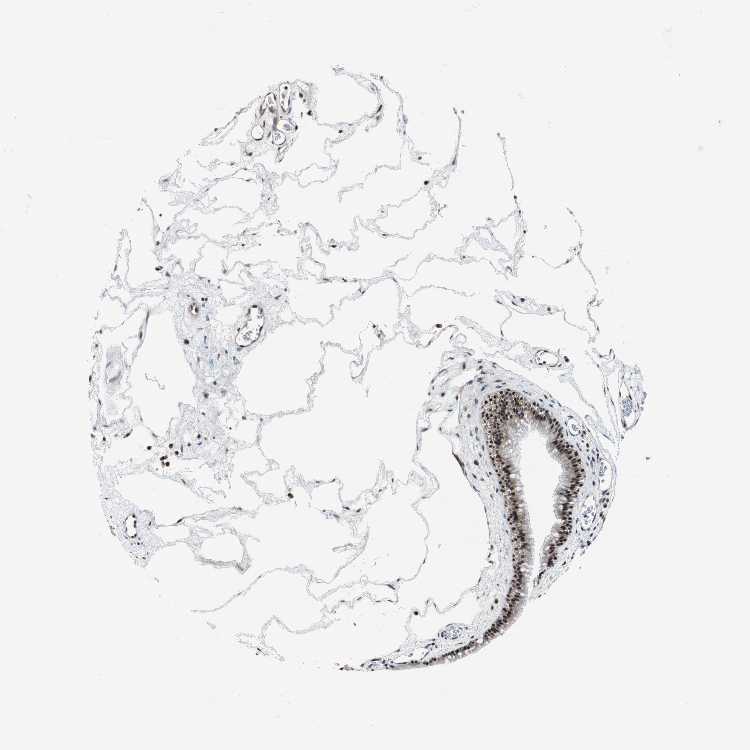

TISSUE PRIMARY DATA NASOPHARYNX Show tissue menu

NASOPHARYNX - Antibody stainingi

Antibody staining in the annotated cell types in the current human tissue is reported as not detected, low, medium, or high, based on conventional immunohistochemistry profiling in selected tissues. This score is based on the combination of the staining intensity and fraction of stained cells.

Each image is clickable and will lead to virtual microscopy that enables deeper exploration of all samples and also displays staining intensity scores, fraction scores and subcellular localization as well as patient and tissue information for each sample.

Antibody HPA006288Antibody HPA007010Antibody CAB000083

Respiratory epithelial cells MediumHighHigh